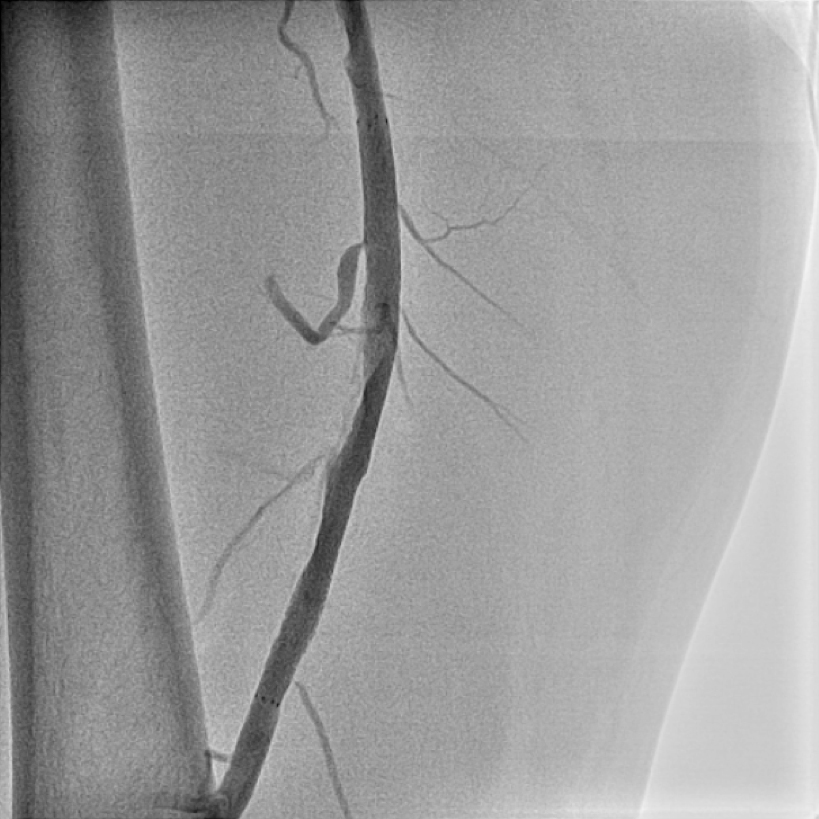

治療には、薬物治療、運動療法、カテーテル治療、バイパス手術、血管新生療法などがありますが、短期間の入院で血流の改善が望めるカテーテル治療は患者負担と治療効果の面から優れた治療法と言えます。(図5、6)

【図6】下肢造影カテーテル治療後 カテーテル治療を行い、血流再開いたしました。